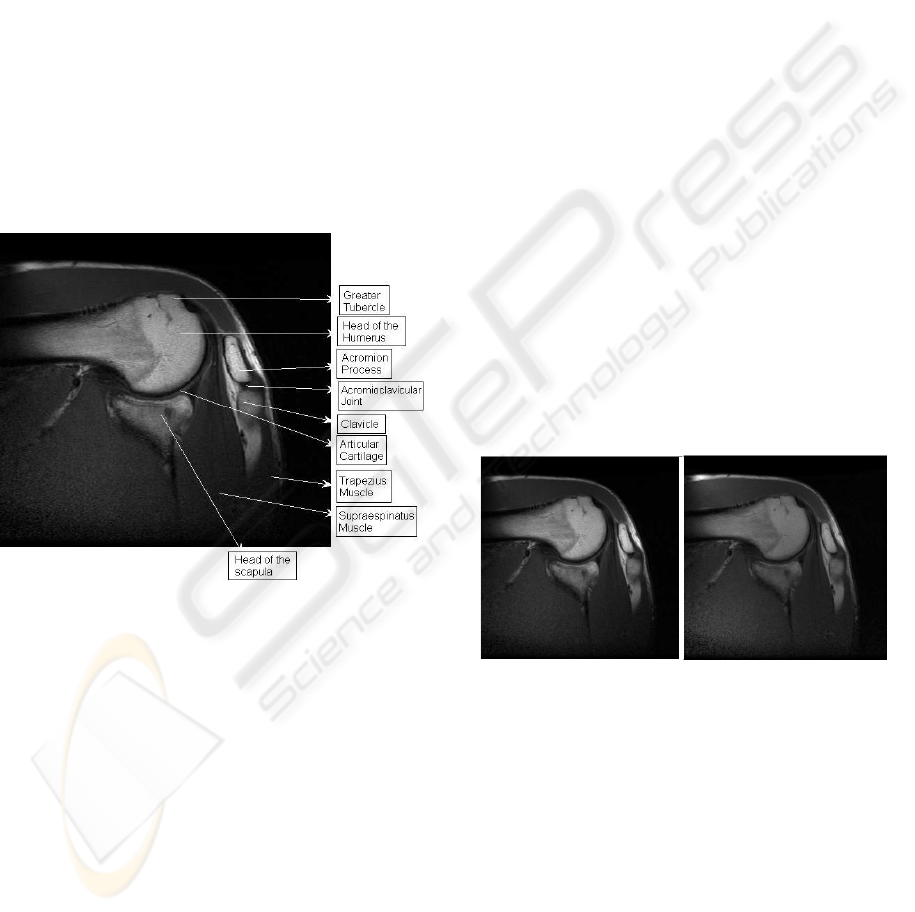

Figure 5: Slice 1. Segmentation image for two phases (4

classes) a) k-means b) Density mixture c) Active contours

As aspected, some more differences between the

quality reconstruction of the different methods can

be appreciated in the multiphase (four classes) clas-

sification problem. In Figures 5-6 we report the re-

sults obtained with the classical (k-means) algorithm

(left), the bayesian mixture model (center) and the

Chan-Vese model (right). The greater tubercle and

the head of the humerus are properly classified and

shaped with our methods (center and right) while the

classical k-means fails in both aspects (and in both

slices, see Figures 5-6, on the left, where the bone

is under-estimated and muscle is wrongly detected).

Articular cartilage has been detected in (center and

right) but not in (left). Muscle is properly classified

with the Chan-Vese model (right) and the classical

method (left) but no classification has been done in

the bayesian approach where the background is as-

signed to the same class. At the same time the head of

the scapula has been properly classified in (right) but

not in (center) where the shape, nevertheless is cor-

rectly obtained. Notice also that the acromial process

has been characterized by the two methods.

Figure 6: Slice 2. Segmentation image for two phases (4

without edges algorithms.